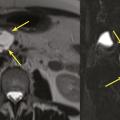

Les TIPMP sont des lésions canalaires intra-épithéliales développées aux dépens des canaux pancréatiques (principal ou/et secondaires) [fig. 1]. Elles prédominent au niveau de la tête et du crochet, mais peuvent concerner toute la glande. La composante kystique des TIPMP présente un épithélium de type mucineux avec production de mucus. Au cours du processus d’oncogenèse, des papilles commencent à se former, et différents phénotypes cellulaires distincts ont été décrits, corrélés à leur pronostic.

Toujours parmi les LKP rares à potentiel malin, on compte les tumeurs neuro-endocrines (TNE) kystiques (20 % des TNE pancréatiques) [fig. 5]. De découverte fortuite et non fonctionnelles, les TNE kystiques sont uniques, uniloculaires, bien différenciées, de bas grade, c’est-à-dire avec un indicateur de prolifération Ki67 < 3 %, et la présence d’une masse hypervasculaire (nodule) au niveau de la paroi. La partie charnue tissulaire peut être de petite taille.